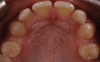

A 16-year-old female patient presented with the chief complaint that she was dissatisfied with the appearance of her anomalous maxillary lateral incisors (teeth Nos. 7 and 10) and multiple diastemas (Figure 1 through Figure 4). She had been referred for restorative treatment after an initial consultation with the orthodontist. Her first restorative appointment was dedicated to data collection, which included a health history and physical examination as well as the acquisition of photographs (facial, dentofacial, dental), videos (chief complaint, F sound, S sound), vinyl polysiloxane (VPS) impressions, a panoramic radiograph, a bite registration, and a facebow registration. The clinical examination revealed that both of the patient's maxillary lateral incisors were peg-shaped. After a discussion about the risks and benefits of different treatment options, such as direct composite restoration, indirect composite veneers, and porcelain laminate veneers, she chose to have her maxillary lateral incisors treated with direct composite buildup restorations. The index cutback technique was chosen for this case instead of a freehand technique in order to create a new shape according to an ideal wax-up but also to be able to control the thickness of the enamel layer.7